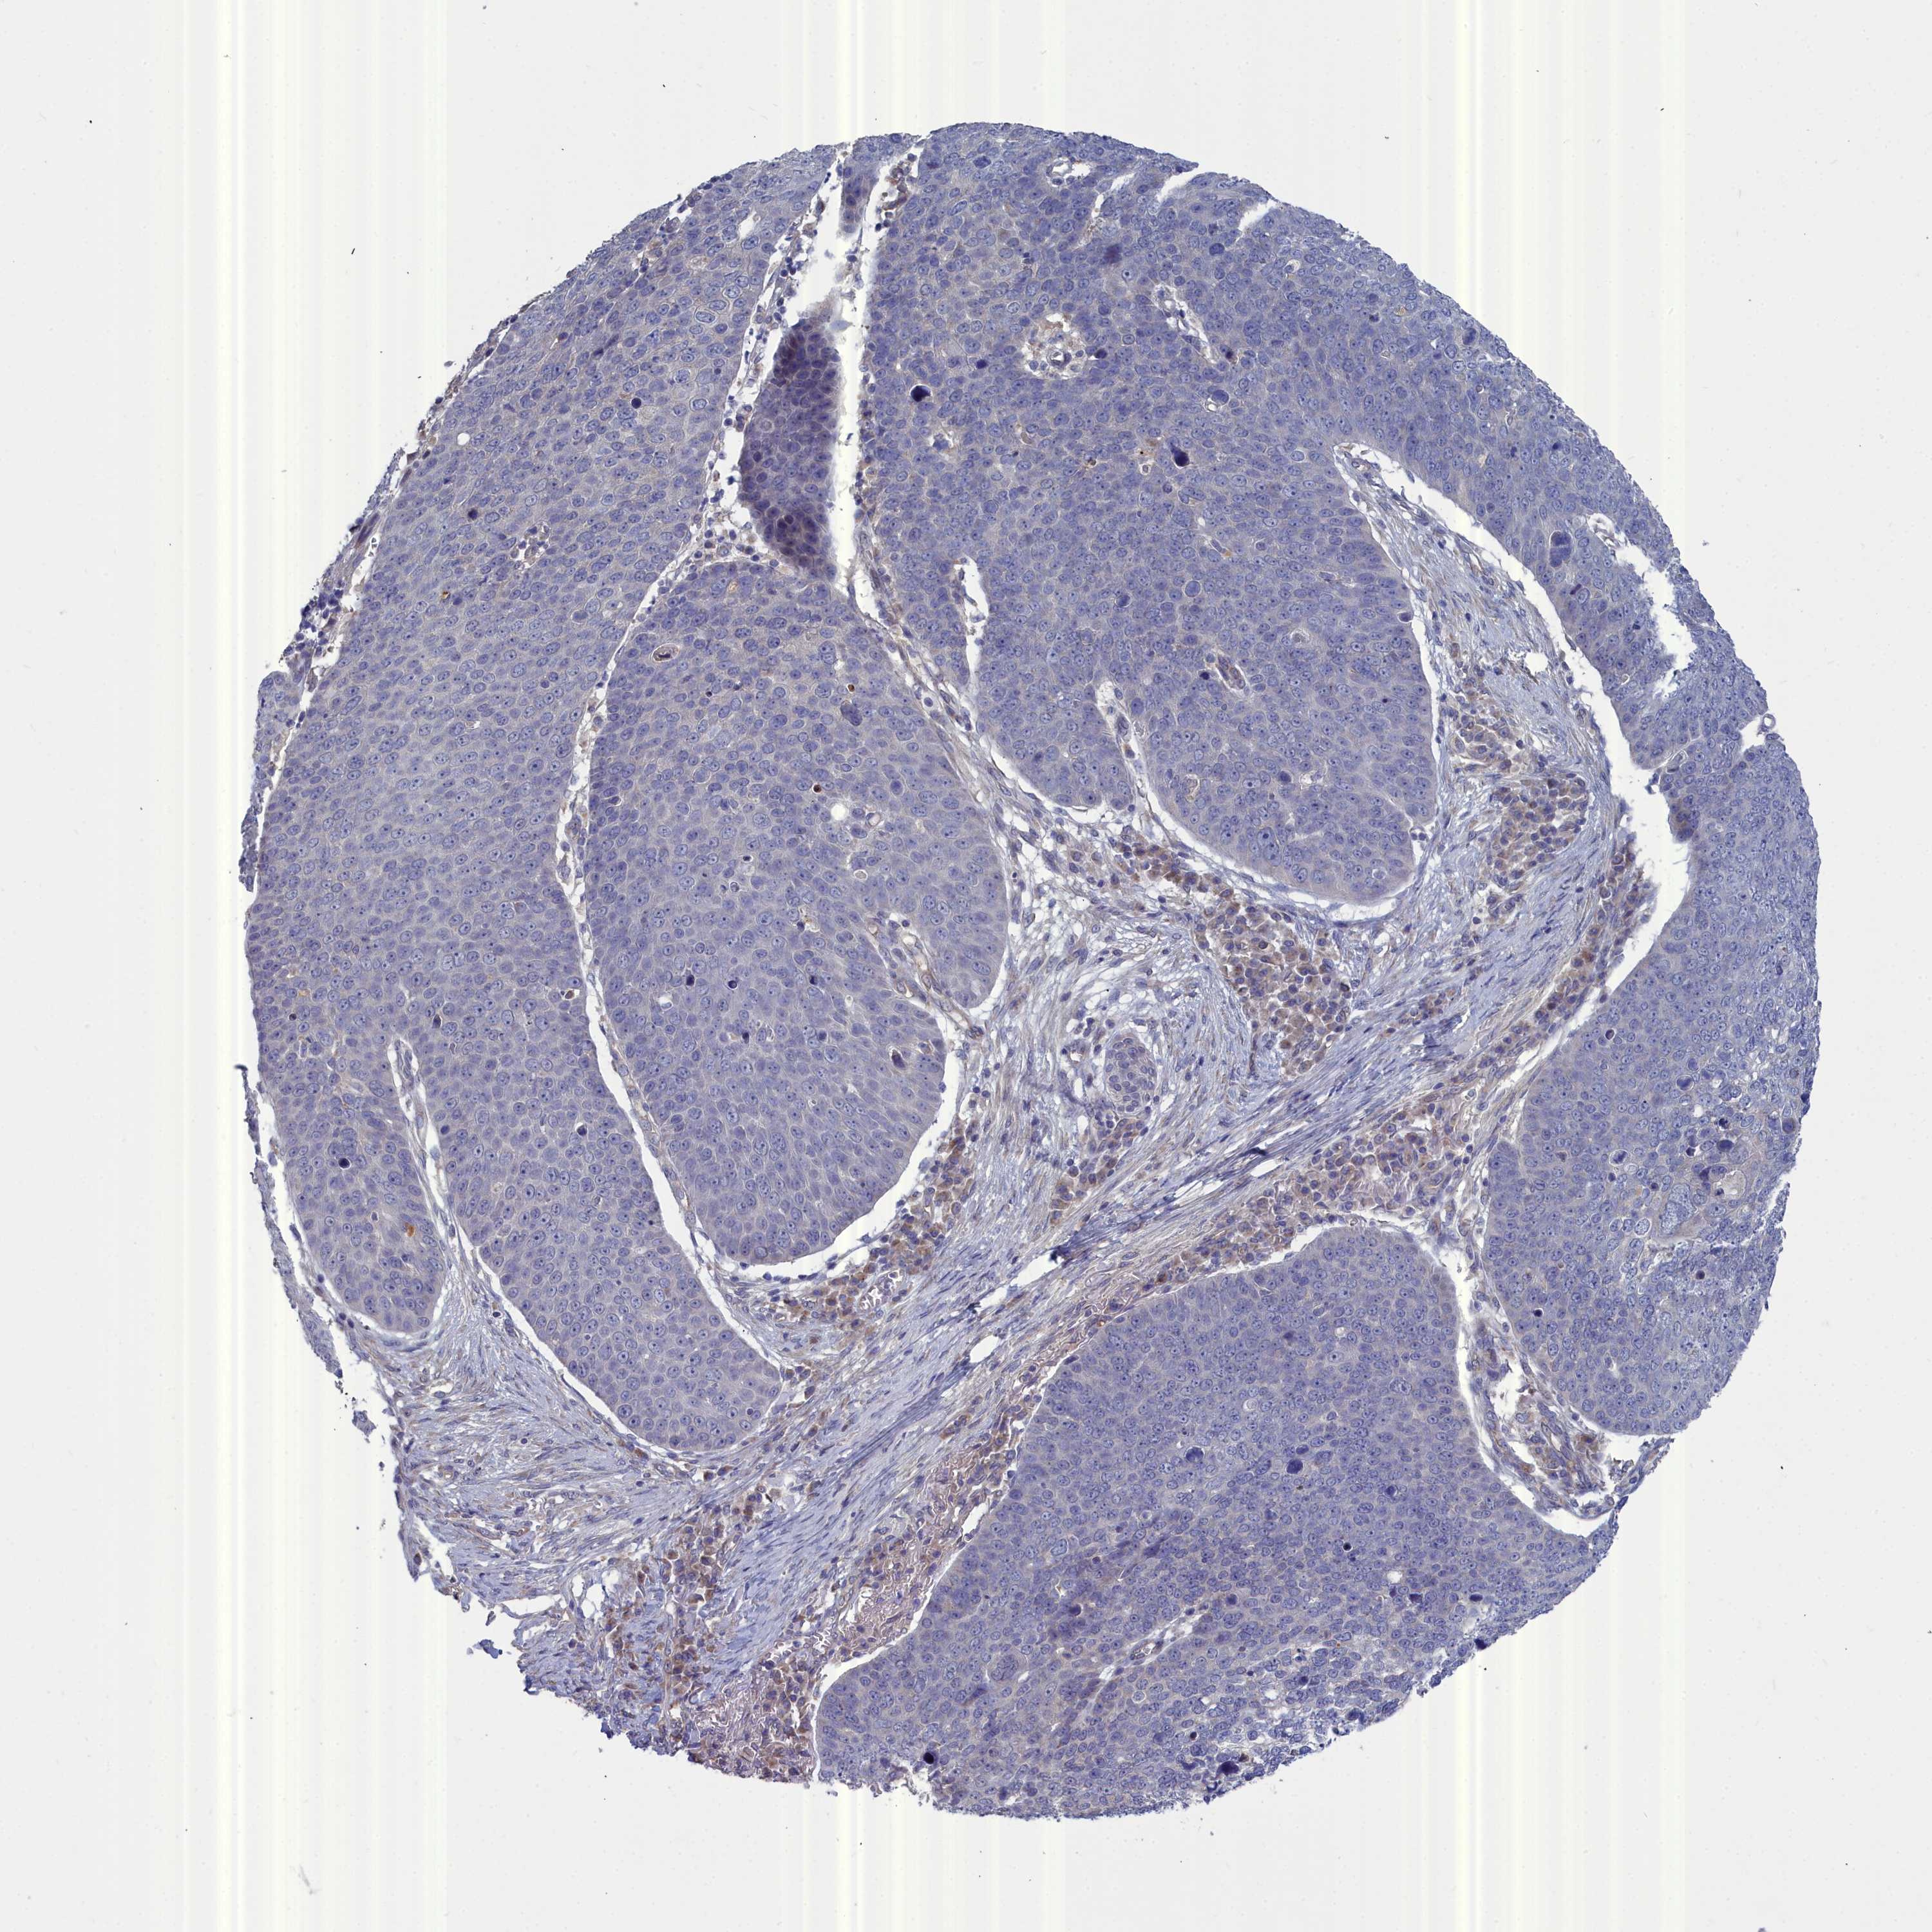

SKIN CANCER - Protein expressioni

A mouse-over function shows sample information and annotation data. Click on an image to view it in a full screen mode. Samples can be filtered based on level of antibody staining by selecting one or several of the following categories: high, medium, low and not detected. The assay and annotation is described here.

Each image is clickable and will lead to virtual microscopy that enables deeper exploration of all samples and also displays staining intensity scores, fraction scores and subcellular localization as well as patient and tissue information for each sample.

Antibody HPA000763

Staining

High

Medium

Low

Not detected

Intensity

Strong

Moderate

Weak

Negative

Quantity

>75%

75%-25%

<25%

None

Location

Nuclear

Cytoplasmic/membranous

Cytoplasmic/membranous,nuclear

Basal cell carcinoma

Squamous cell carcinoma, NOS

Squamous cell carcinoma, metastatic, NOS